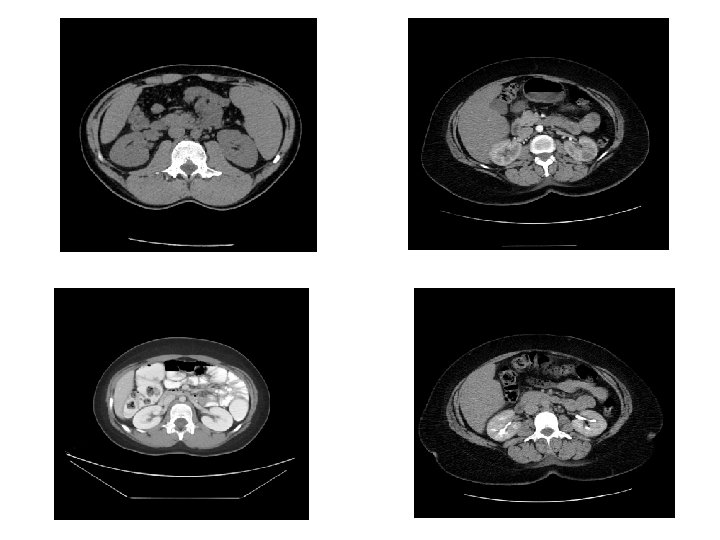

CT • Same basic principle of radiography. • More precise. • Costly. • +/- contrast. • Useful for trauma, stone, tumor, infection.

CT Image features: • Cross sectional images. • Image contrast determined by tissue density +/- contrast. • Better evaluation of soft tissue.

CASES

• What are the imaging modalities? • What are the findings? • Diagnosis?